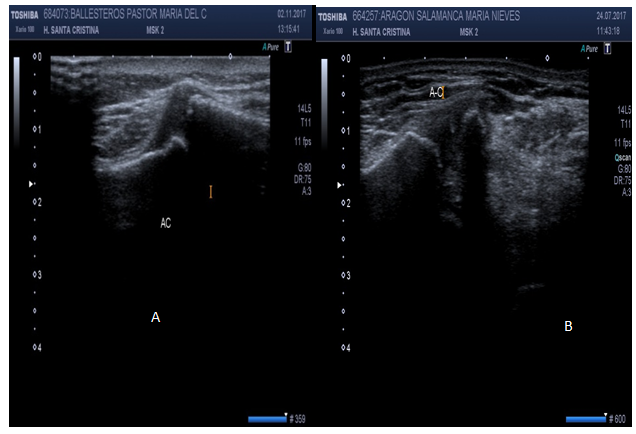

US can ascertain between normal versus diseased bicipital tendon (partial or full tears, tendinosis). Hyperechoic “fluid ring” around tendon may denote tenosynovitis in short axis, whether a “tear sign” may denote tenosynovitis in long axis (Figure 14). US may identify osteophytes in AC joint and joint effusion (“Geyser Sign”) if inflammation subsides (Figure 15). Small calcific areas in the tendon can be observed specially when assessed dynamically (Figure 16). US is highly sensitive to diagnose SASD bursitis, especially if fluid on scan image is greater than 2mm distance (Figure 17). Dynamic evaluation is capable to determine biceps tendon subluxation or luxation and subacromial impingement (Figure 18).

Figure 17 Subacromial subdeltoid bursitis greater than 2mm.